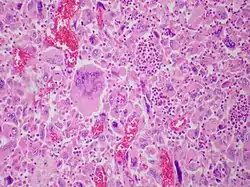

Pulmonary giant cell carcinoma represents a rare variety of non-small cell lung carcinoma that is characterized by the presence of numerous tumor giant cells and an influx of inflammatory cells that are mostly polymorphonuclear leukocytes admixed with macrophages. The dense oval aggregates of polymorphonuclear leukocytes seen in this image are probably located in the cytoplasm of tumor giant cells (emperiopolesis) that have been sectioned in a plane that does not include their nuclei.

The characteristic feature of this highly lethal malignancy is the distinctive light microscopic appearance of its extremely large cells, which are bizarre and highly pleomorphic, and which often contain more than one huge, misshapen, pleomorphic nucleus ("syncytia"), which result from cell fusion.

Both "tumor cell-tumor cell" and "leukocyte-tumor cell" emperipolesis (i.e. active penetration of the latter by the former) is very commonly seen in cases of GCCL.[12]